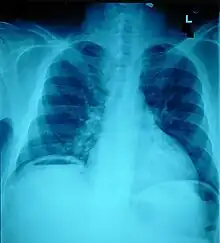

The small intestine takes up a large part of the abdomen and is likely to be damaged in penetrating injury.[5] The bowel may be perforated.[4] Gas within the abdominal cavity seen on CT is understood to be a diagnostic sign of bowel perforation; however intra-abdominal air can also be caused by pneumothorax (air in the pleural cavity outside the lungs that has escaped from the respiratory system) or pneumomediastinum (air in the mediastinum, the center of the chest cavity).[4] The injury may not be detected on CT.[4] Bowel injury may be associated with complications such as infection, abscess, bowel obstruction, and the formation of a fistula.[4] Bowel perforation requires surgery.[4]